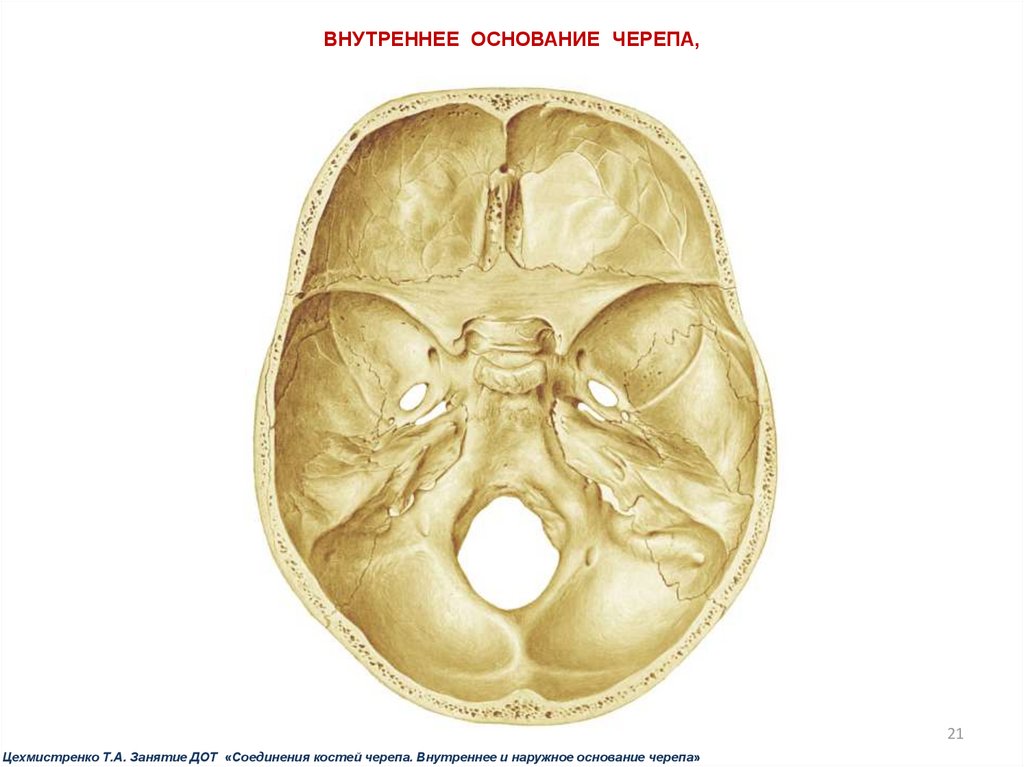

Анатомические детали: Фотографии топографии черепа с нижнего вида